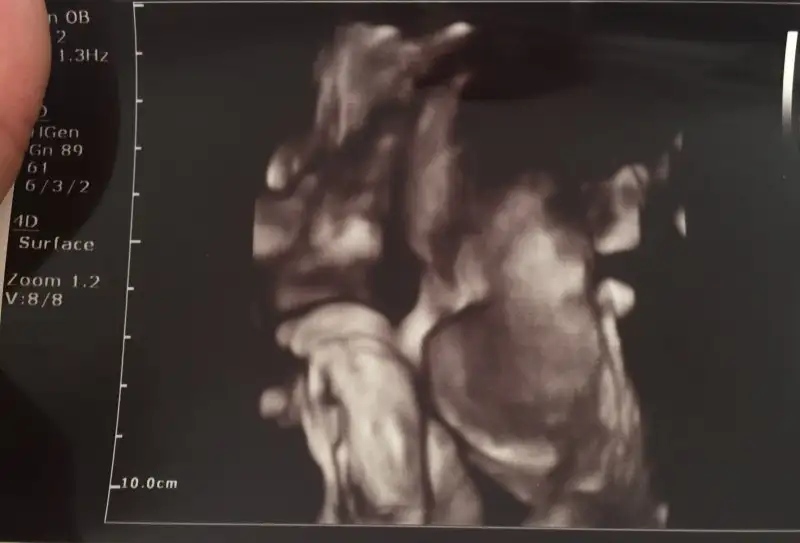

Arkadaşlar uzun zamandir yazmıyorum ama takipteyim bizim bu sabah randevumuz vardı cumartesi günü nişanım gelmişti rahim ağzı yumuşamış ama sancılarım yok oglusum ilk defa yüzünü gösterdi. Yalnız plasenta aşağıya inmiş kısmen kapatıyormuş rahim ağzını bu zamana kadar yukarıdaydi normal doğuma engel değil şimdilik dedi çatı muayenesi yaptı o da güzel dedi. Bu da benim aylardır yüzünü göstermeyen inatçı oğlum babaya benzetti annemler